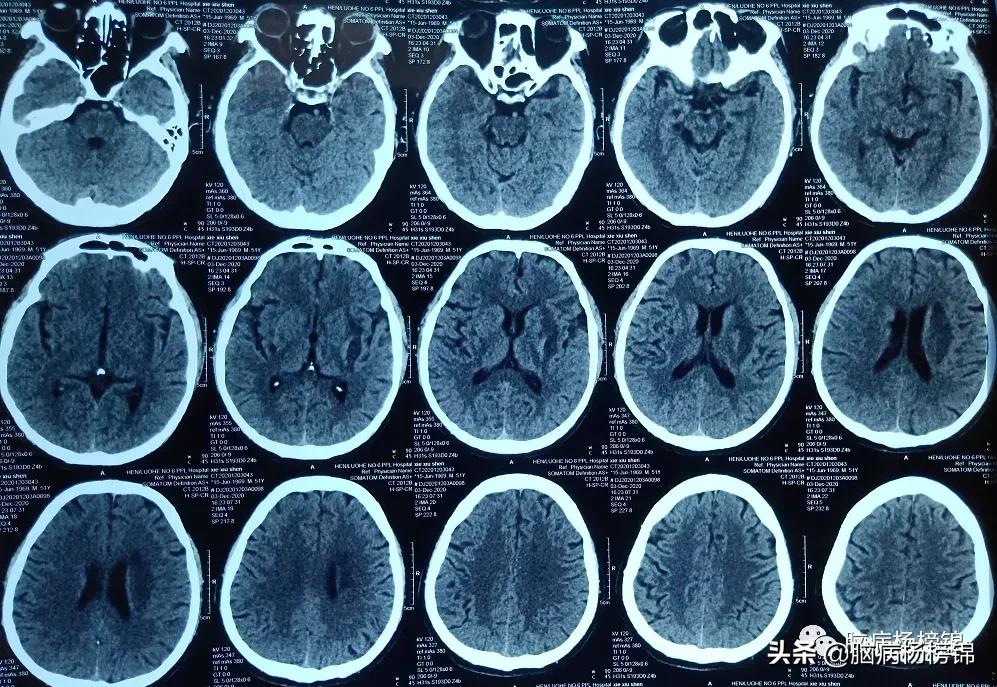

漯河市第一人民医院急诊颅脑CT,脑出血。

保守治疗六天,病情稳定。

保守治疗16天,血肿开始吸收。

保守治疗25天,血肿大部分吸收。转入漯河六院康复医学科。

发病两个月的片子,遗留软化灶。